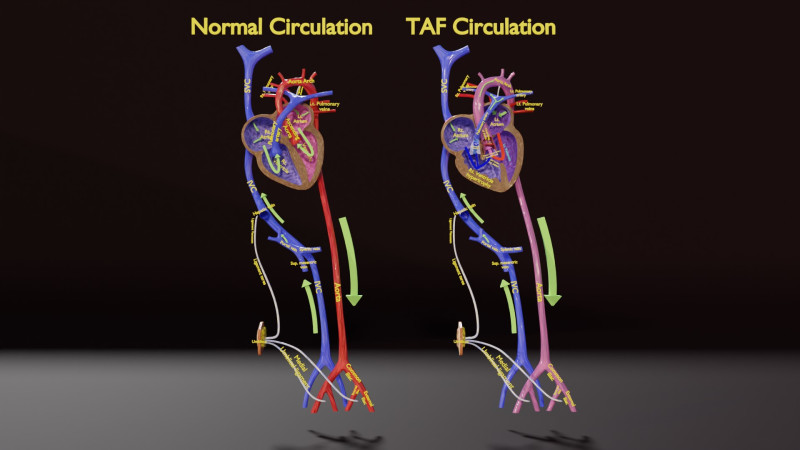

The model meshes include adult circulation versus circulation in Tetralogy of Fallot (TAF), arrow labels and text labels. The blood flow in a patient with Tetralogy of Fallot is outlined in this model. To contrast it to normal blood circulation a separate model of normal circulation is included. The Tetralogy of Fallot (OVER RIDING OF AORTA, PUL STENOSIS, VENTRICULAR SEPTAL DEFECT, RIGHT VENTRICULAR HYPERTROPHY), fossa, ligament teres , venosus, and arteriosus are duly depicted with proper labelling and blood flow directional arrows. Excellent model for teaching, demonstration and knowlegde of human body. The models include both procedural and image textures blend files separately. The texture file include diffuse, roughness and normal png and jpeg based on non overlapping UV maps.